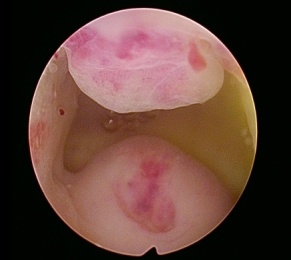

宫腔镜下的子宫内膜息肉

子宫内膜息肉像子宫内壁长出的“小肉赘”,多数为良性但可能影响生活。经期延长就像关不紧的水龙头,月经期间内裤上偶尔看到一点褐色或红色的血迹,量很少,时有时无。基于目前研究,估计育龄期、围绝经期及绝经后人群总体患病率为7.8%~34.9%。

(1) 宫腔镜检查

采用宫腔镜经过阴道及宫颈进入宫腔,查看宫腔内情况。这一方法可以明确诊断,排除恶性病变,而且经自然腔道给患者带来的创伤小。

✂宫腔镜下子宫内膜息肉切除术

主要适用于绝经前有症状,合并不孕症及辅助生殖技术治疗前,有恶变高危因素,息肉直径>1厘米,复发性、药物治疗效果不佳及绝经后子宫内膜息肉。

该术主要优点有经济成本低、手术风险小、不适程度低、经自然腔道无切口、恢复快、出血少、住院时间短。